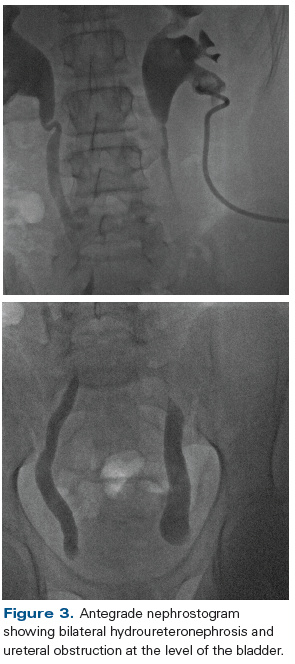

Figure 3. Antegrade nephrostogram showing bilateral hydroureteronephrosis and ureteral obstruction at the level of the bladder.

Postoperatively, neither his serum creatinine level nor his hydronephrosis was improving, prompting placement of bilateral percutaneous nephrostomy tubes (Figure 3). Afterward, his creatinine level declined progressively over 2 weeks until it stabilized near 1 mg/dL. Unexpectedly, over the next few days, he developed intermittent fever and leukocytosis, which were persistent despite a negative infectious evaluation. In addition, his inflammatory markers were consistently and significantly elevated, with an erythrocyte sedimentation rate (ESR) of 127 mm/hr and a C-reactive protein (CRP) level of 16.8 mg/dL, both of which were many times the upper limit of normal values. He continued to suffer severe bladder spasms even though he was receiving regularly scheduled doses of antispasmodics.